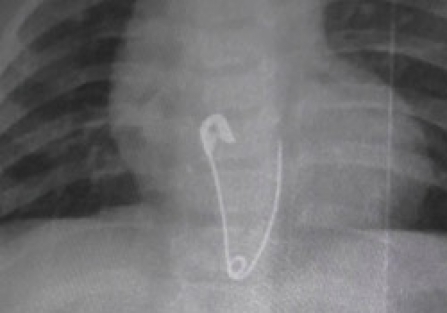

Bir süre sonra ailesi tarafından fark edilen bebeğin oynağı iğnelerin eksik olduğu anlaşıldı. Yapılan aramada eksik olan çengelli iğneyi bulamayan aile, çengelli iğneyi bebeklerinin yutmuş olabileceğini düşünerek Kulu Devlet Hastanesi’ne başvurdu. Çekilen röntgende çengelli iğnenin bebeğin yemek borusunda olduğu belirlendi. Bunun üzerine 8 aylık bebek iğnenin çıkarılması için Ankara’ya sevk edildi.